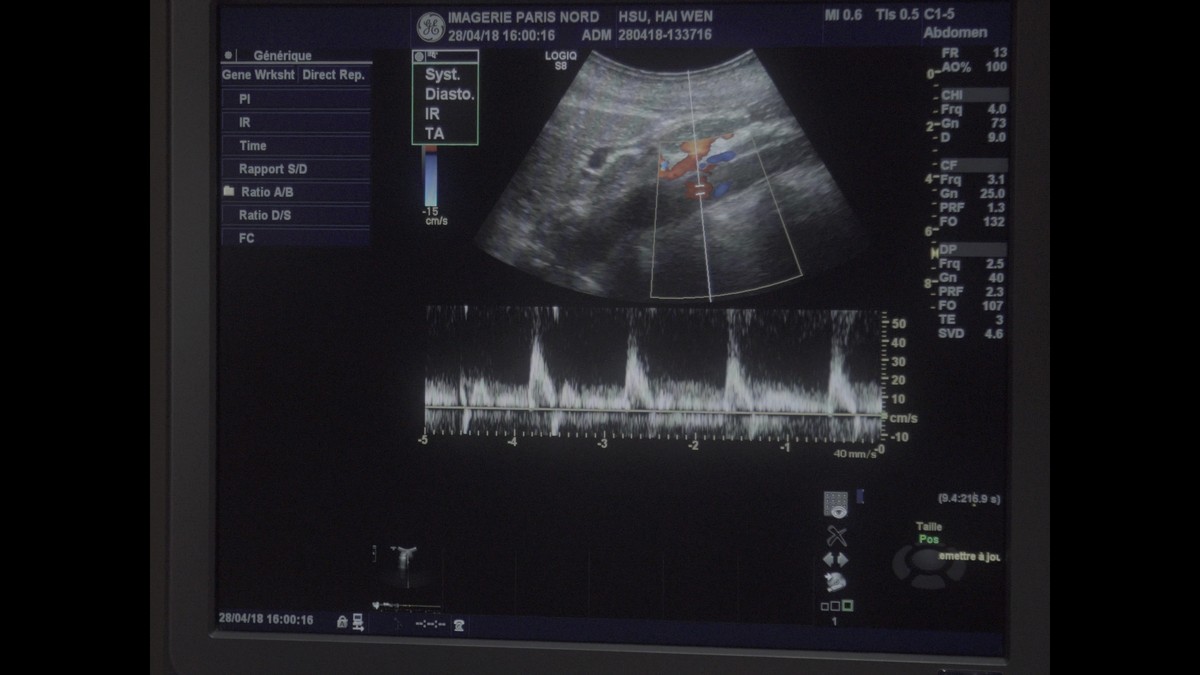

A travers ce film, j’ai voulu trouver, interroger ce dédoublement, en détournant les images médicales de leur usage initial. Grâce à la kinésiologie, j’expérimente un rapport différent au corps, mettant sa propre vie en évidence.

L’expérience de cette réalisation montre de façon saisissante l’intériorité du corps comme un environnement proche de la mer. L’eau offre une vaste gamme d’expressions.

Mon travail consiste à explorer la notion de dédoublement, les relations entre corps et esprit, en évoquant la sensation et la mémoire du corps. À travers le grossissement visuel de détails du corps, la texture, le contraste des images corporelles, l'association et la fusion d'images et le langage d'expression corporelle, cette recherche fait apparaître des problèmes d'intérêt immédiat.

Un grand merci à Gao Bo, au docteur François Lapeyre et l’équipe de l’Imagerie Paris Nord, Sarcelles, les Kinésiologues Delphine Gallien, Ana Delaperrière, Jean-Luc Penet, mes amis à Taiwan.